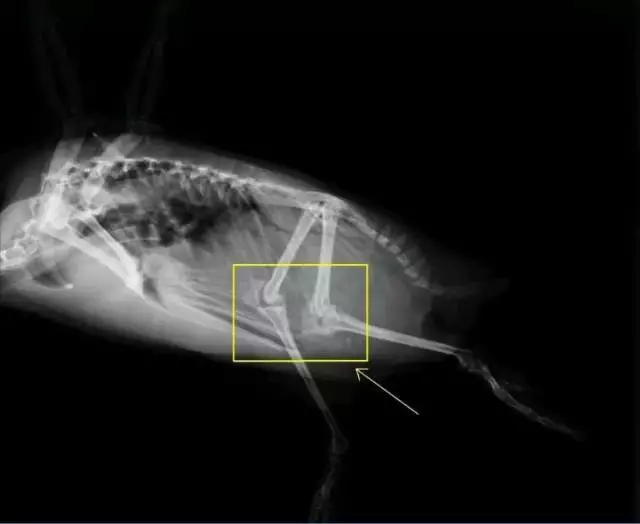

鸡的膝盖为什么往后弯

不光是鸡,所有的鸟类,看起来膝盖都是往后弯的。这是为什么呢?

因为它们的腿和我们结构不太像。好,现在请你站起来,做一个踮脚的动作。感受一下。所有的鸟类,它们的脚相当于我们的腿踮起来:踮起之后,我们的脚趾和前脚掌,相当于鸟的脚掌;我们的前脚掌到脚踝的部分,相当于口语中鸟的小腿或琵琶腿;我们的小腿,相当于鸟的大腿;而我们的大腿,就是更上面大的那一截。

所谓“鸡的膝盖向后弯”,真相是,那不是膝盖,那是鸡的脚后跟。

鸵鸟和人的腿骨对比。

鸡站立时腿部的姿势,和我们踮着脚蹲下来差不多。